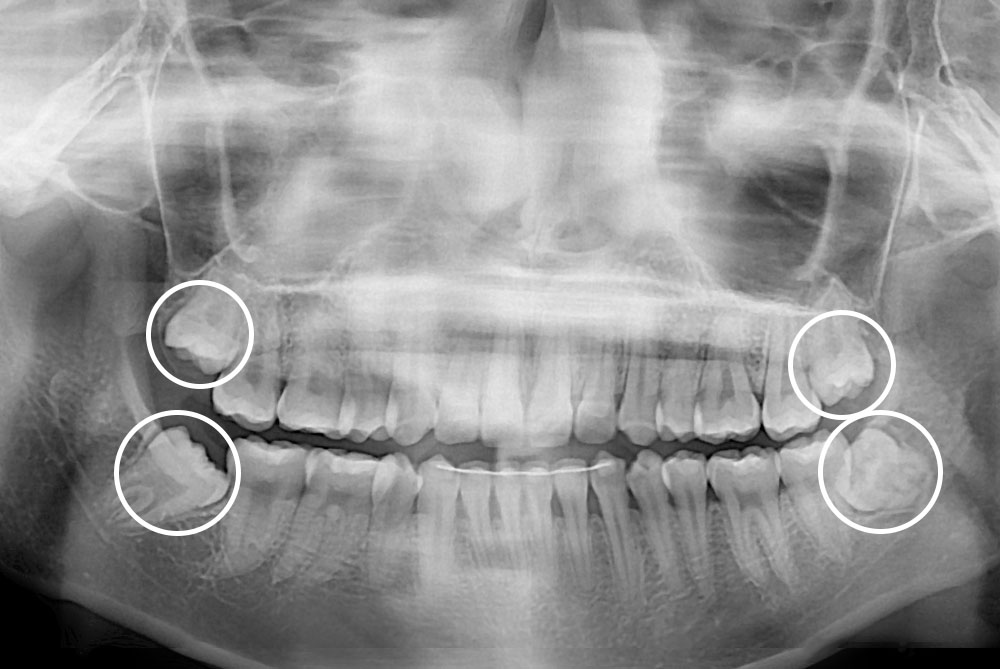

[사랑니] 매복 사랑니 발치

치료전 : 2019-06-04